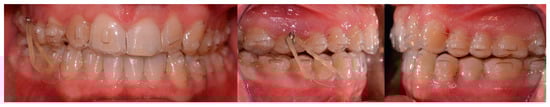

2.2. Clinical Findings

2.3. Diagnostic Assessment